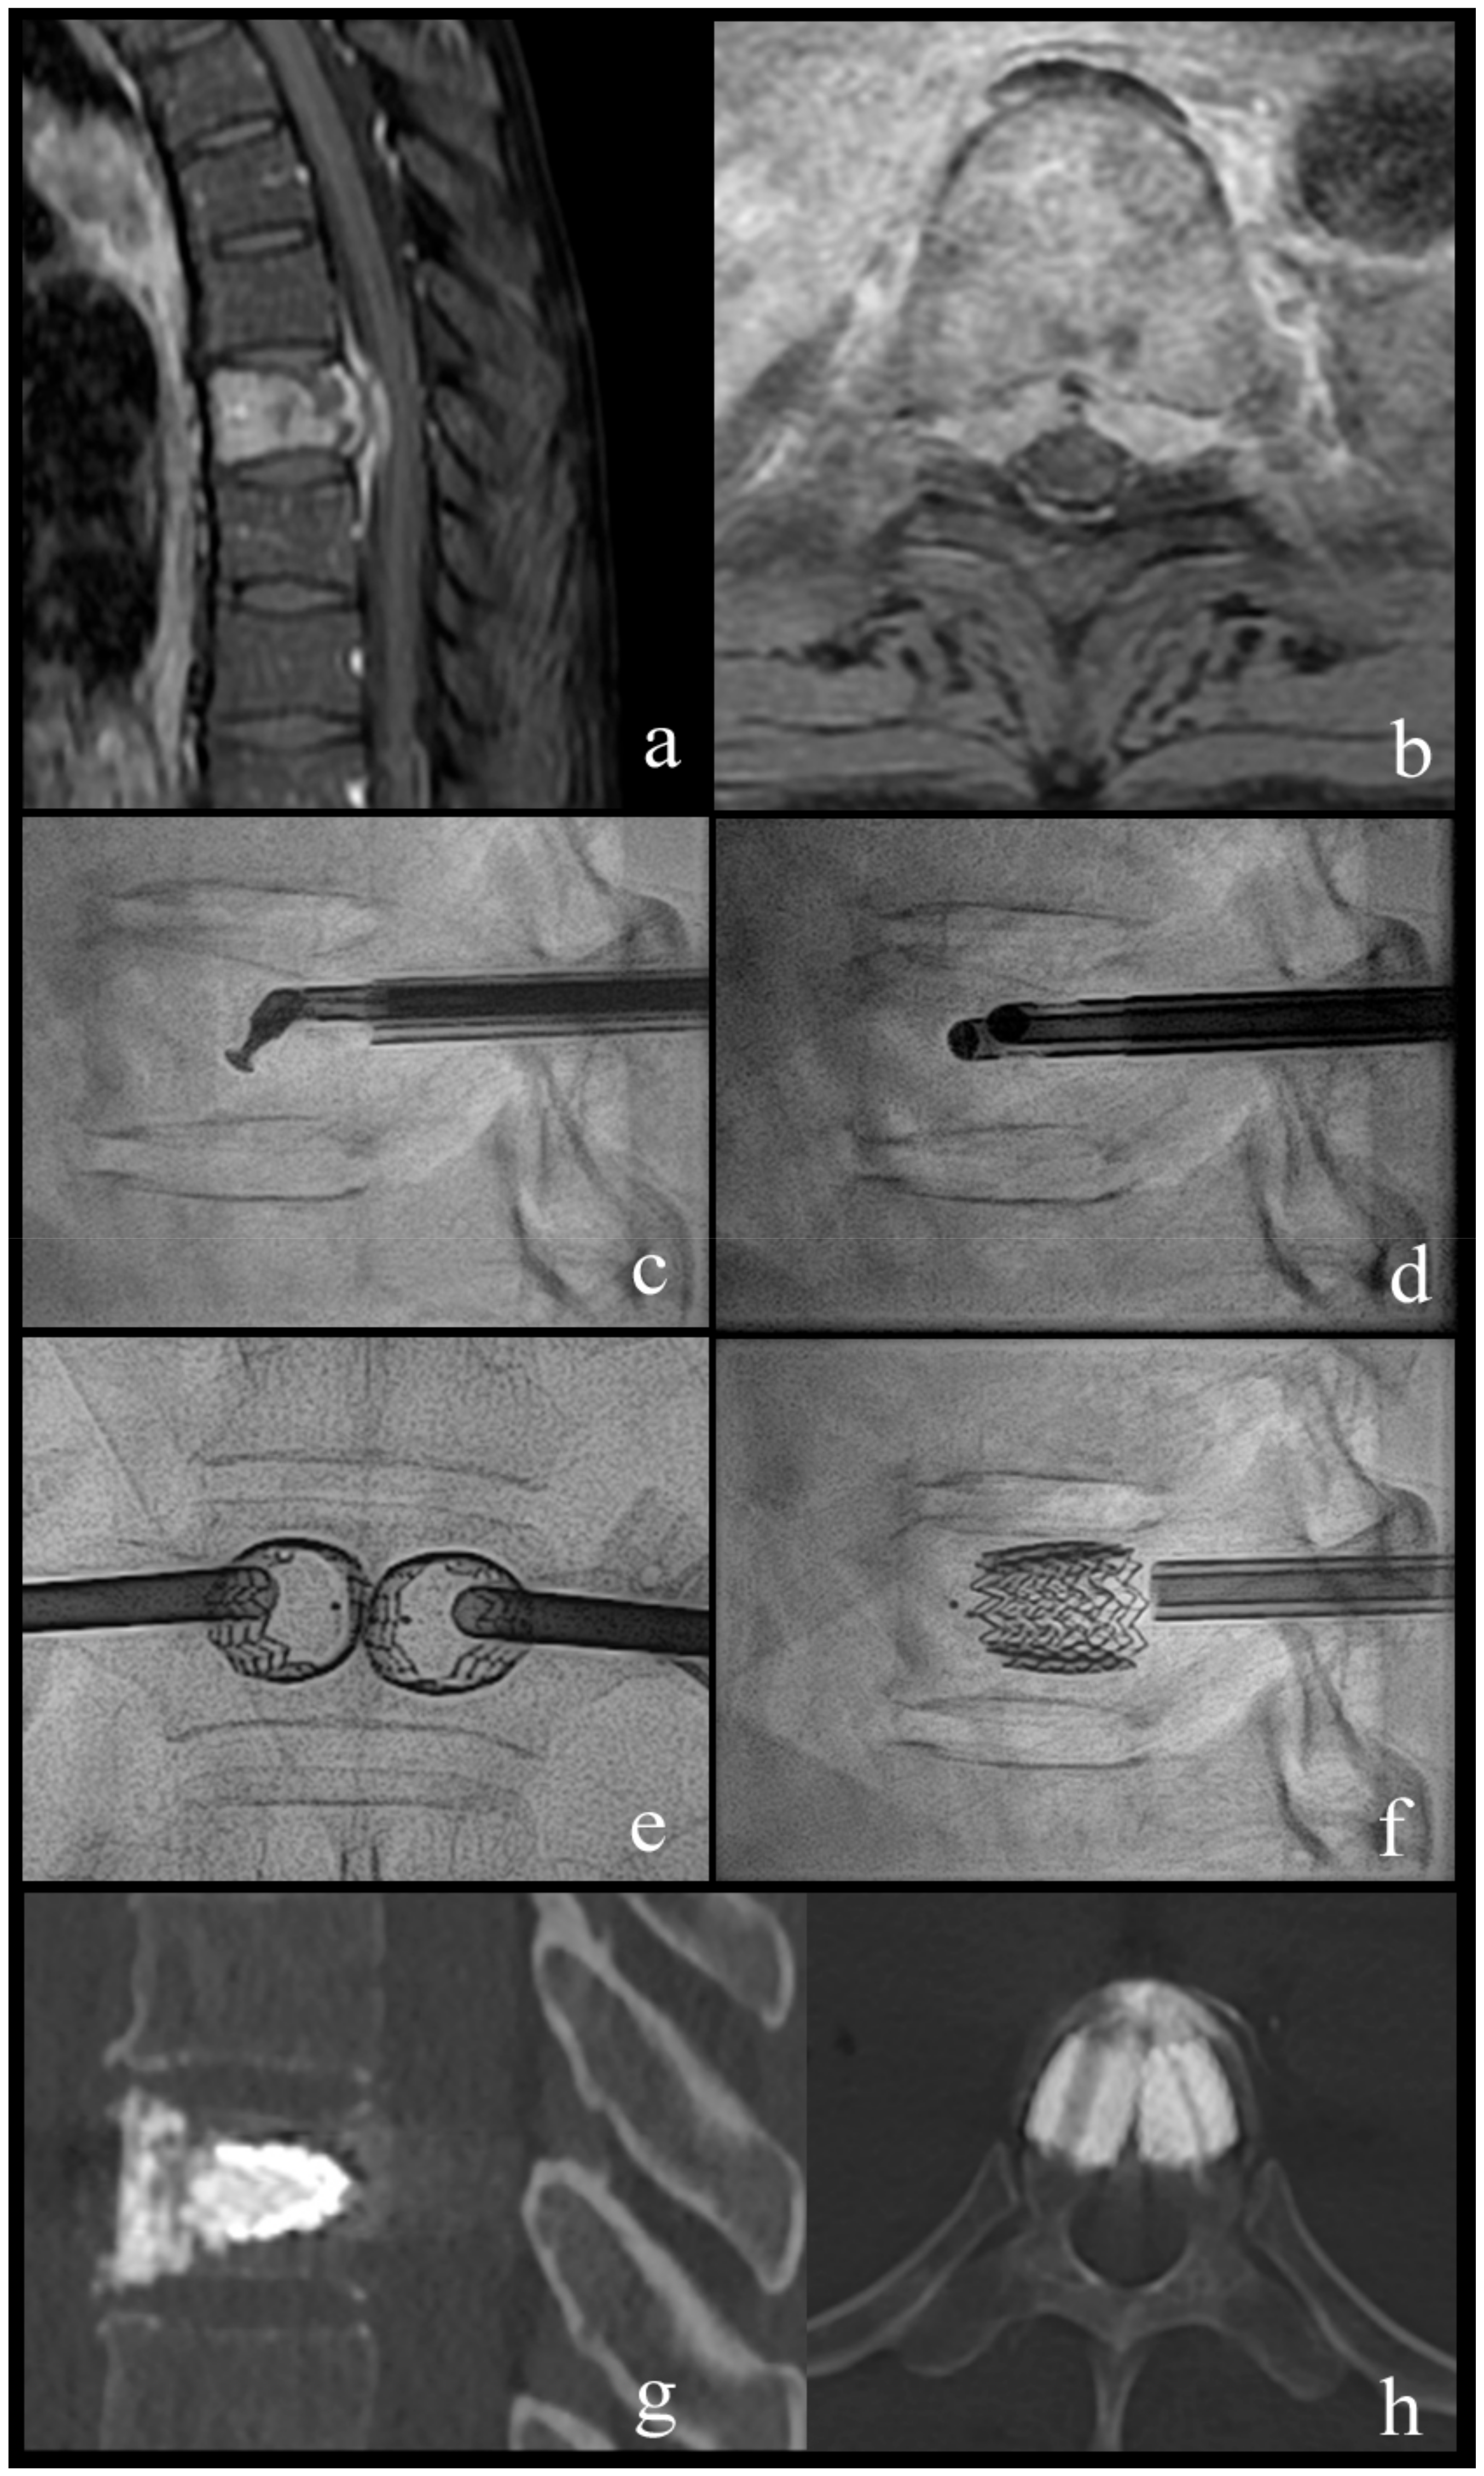

Mechanical Cavity Creation with Curettage and Vacuum Suction (Q-VAC) in Lytic Vertebral Body Lesions with Posterior Wall Dehiscence and Epidural Mass before Cement Augmentation

Procedural Details